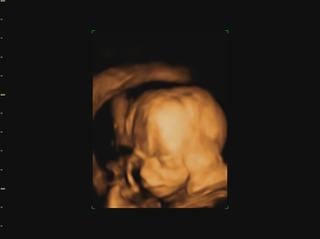

Ahojte kočky, konečne mam trošku času tak si idem spätne prečítať čo ste napísali... a pochváliť vám krásne brušinká 😀 medzi tým Vám pridám moje brušo a našu Izzy neposednú. Máme aj video, ale to som dala len FB, lebo tu sa pridať nedá. Fotky aj video je trochu rozmazané, lebo mala v kuse so sebou narabala... a ano pipik nam nedorastol... 😀